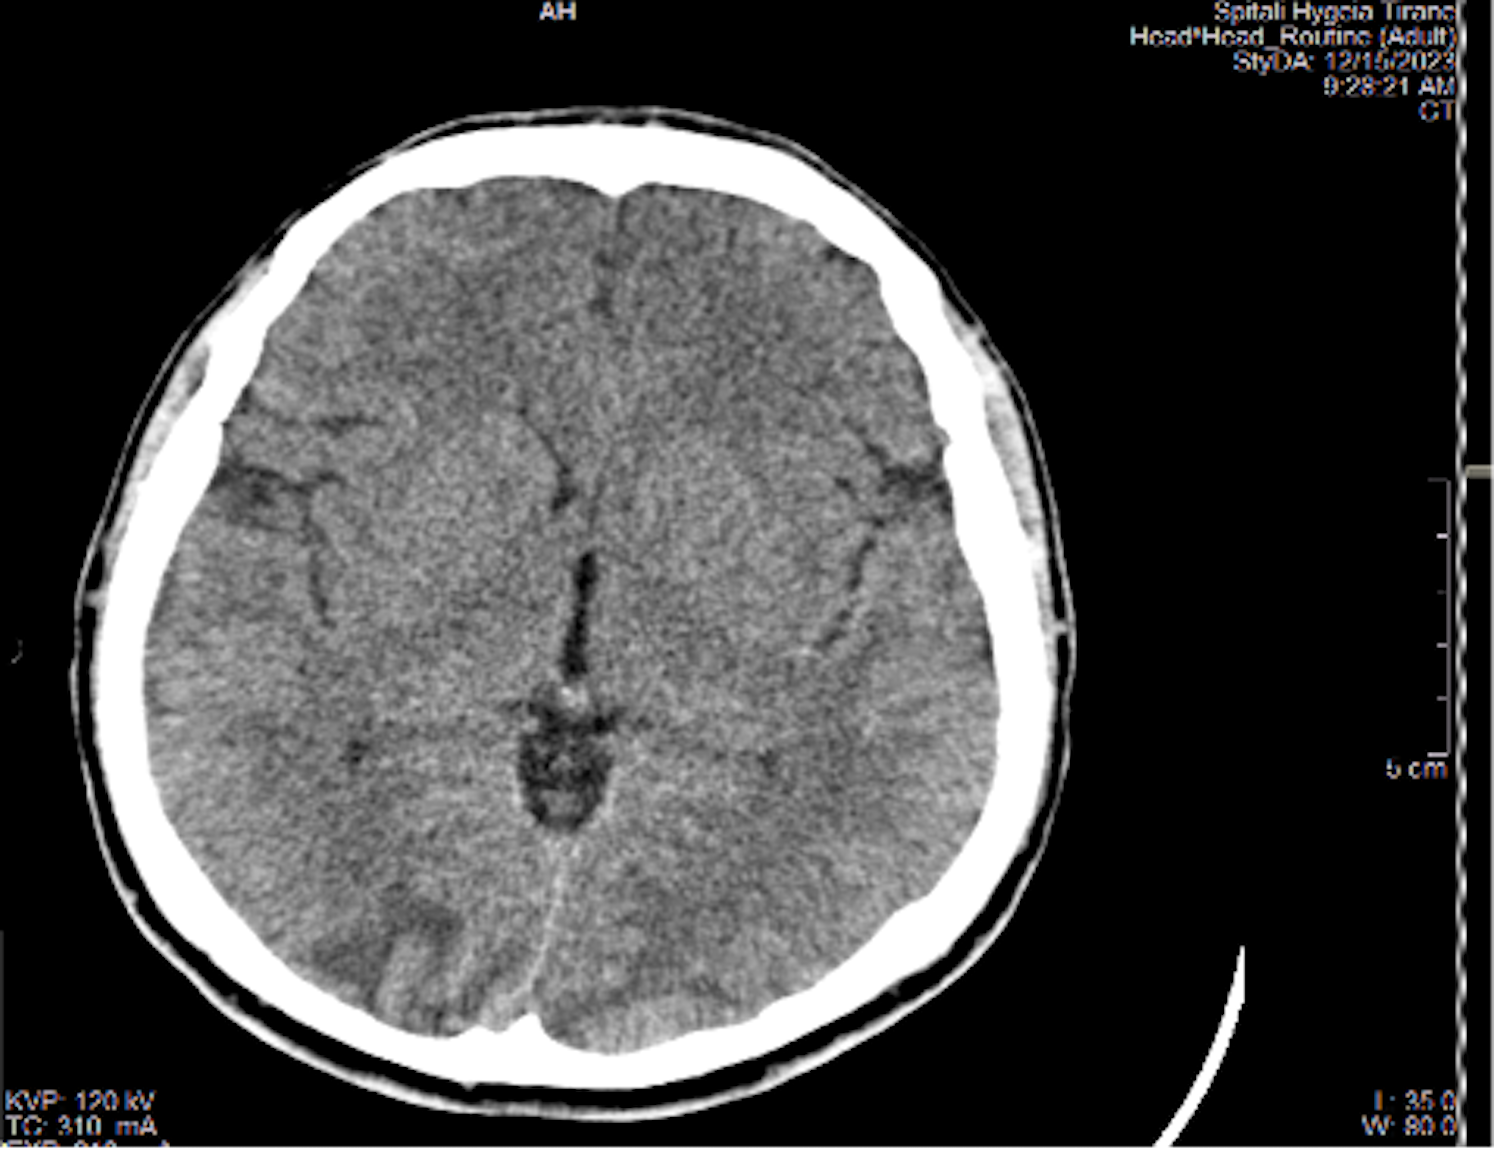

Results: A 23-year-old male patient who had been receiving dialysis for four years underwent a kidney transplant with a living donor - his mother. The primary disease leading to end-stage renal disease (ESRD) was rapidly progressing glomerulonephritis. At the time of diagnosis, he also had high blood pressure readings which remained uncontrolled during the dialysis period, complicated by left ventricular hypertrophy and hypertensive retinopathy, however, the head MRI was normal. During the last year of dialysis, the blood pressure was normalized under multidrug antihypertensive therapy, which included doxazosin, amlodipine, hydralazine, metoprolol, minoxidil, and irbesartan. Post-transplant surgery, diuresis was immediately established. Induction therapy was conducted with ATG, and maintenance therapy included tacrolimus, MMF, and prednisone. The values of creatinine and urea were decreasing. On the fifth postoperative day, the patient experienced seizures, altered mental status, headaches, and visual disturbances but no neurological deficits. His vital signs stabilized after 2-3 minutes post-seizure with the following parameters: blood pressure 150/90 mmHg, heart rate 110/minute, respiratory rate 17/minute, oxygen saturation 97%, body temperature 36.6°C, lactate level 6 mmol/L, pH 7.35, and bicarbonate (HCO3) 22 mmol/L. The neurologist recommended an urgent head CT scan, which showed Posterior Reversible Encephalopathy Syndrome (PRES). The level tacrolimus of tacrolimus was 8.6 ng/dl.